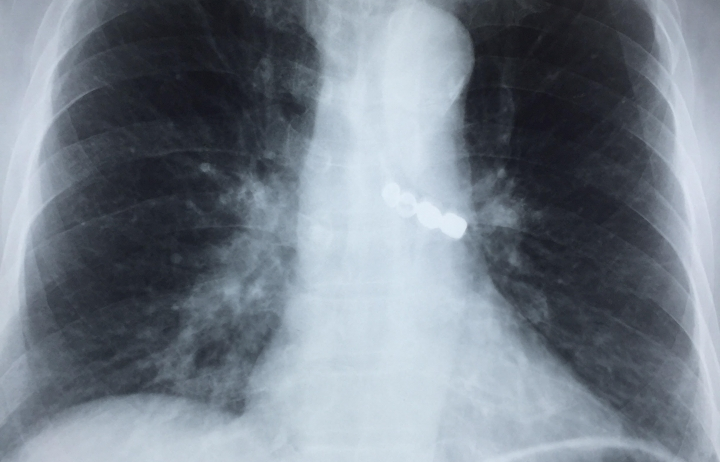

Cứu sống cụ ông rơi cả cầu răng giả vào phế quản

13:55 | 24/09/2018

Bệnh viện Phổi Trung ương vừa tiến hành nội soi phế quản cấp cứu để cứu sống cụ ông 90 tuổi bị rơi cả cầu răng giả 4 chiếc vào phế quản, gây hẹp gần ...